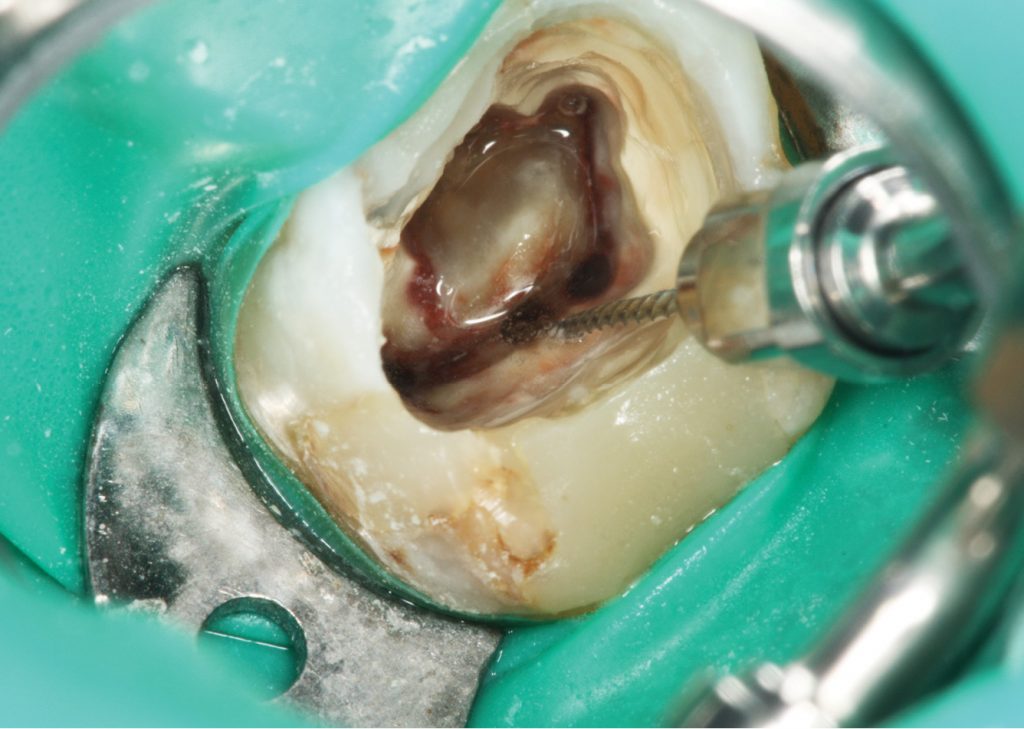

- Opracowanie komory i ujść kanałowych.

- Ponowne leczenie endodontyczne oraz usuwanie wkładów i złamanych narzędzi.